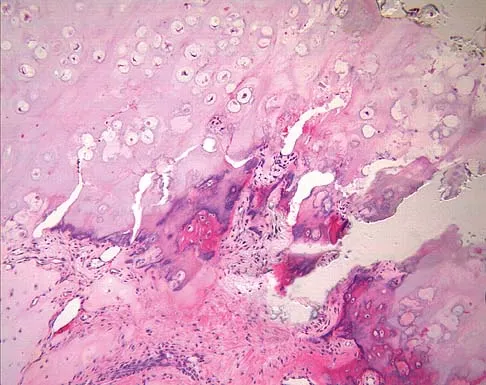

Question 72

A 34-year-old woman reports constant midlateral arm pain after sustaining minimal trauma to the shoulder. Radiographs and a biopsy specimen are shown in Figures 29a and 29b. What is the most likely diagnosis?

Explanation

Eighty percent of giant cell tumors occur in patients older than age 20 years, with the peak incidence in the third decade of life. Most of these tumors are eccentrically located and epiphyseal in location. They are lytic in nature as in this patient. Although named for the hallmarked multinucleated giant cells seen in the lesion, the basic cell type is the spindle-shaped stromal cell. Chondroblastoma is highly cellular and contains large multinucleated giant cells with intercellular chondroid material, some of which is calcified. Chondromyxoid fibroma has chondroid tissue separated by strands of more cellular tissue with occasional multinucleated giant cells. Desmoplastic fibroma is characterized by poorly cellular fibrous tissue, and lymphoma is highly cellular with characteristic round cells. Campanacci M, Baldini N, Boriani S, et al: Giant cell tumor of bone. J Bone Joint Surg Am 1987;69:106-114.